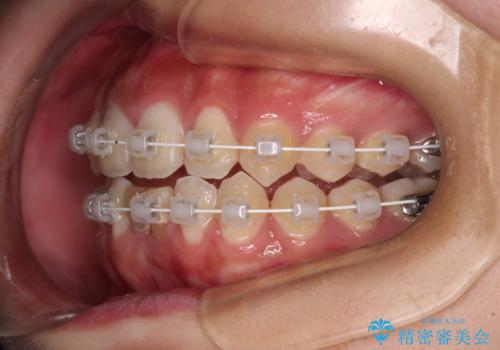

マウスピースでもワイヤーでも対応可能でしたが、自己管理の煩わしさからマウスピース矯正は避けることとしました。

ワイヤー装置により矯正治療を行うとともに舌突出癖改善のためのトレーニングをしっかりと行っていただき、咬み合わせが安定した位置となったタイミングで下顎前歯にブリッジの仮歯を装着していく計画としました。

矯正治療終了後に速やかにオールセラミックブリッジを装着していくこととしました。